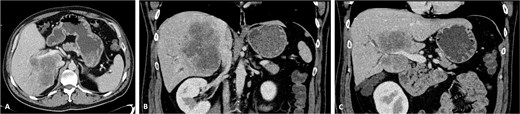

A 42-year-old asymptomatic male patient was referred with a suspicious liver mass detected on abdominal ultrasound (US). The US was made after a blood test revealed an isolated elevation of gamma-glutamyl transferase of 789 IU/l. Past and family history were unremarkable. Computed tomography (CT) scan revealed a large tumour measuring 12.6 cm occupying the right liver (Fig. 1 and Supplementary Video S1). Magnetic resonance confirmed a heterogeneous, ring-enhancing hepatic lesion with obliteration of the right hepatic vein (RHV), and invasion of the middle hepatic vein (MHV), PV, and the retrohepatic portion of the IVC. No metastatic lesions were present. Tumour markers and endoscopic exams revealed no alterations.

CT scan of the intrahepatic cholangiocarcinoma before chemotherapy. (A) Axial CT scan of the intrahepatic cholangiocarcinoma centred in liver segments 5, 7, and 8, with extension to segment 1 and invasion of the PV and IVC; (B) coronal CT scan view of the vascular relation between the cholangiocarcinoma and the IVC; and (C) vascular invasion of the PV.